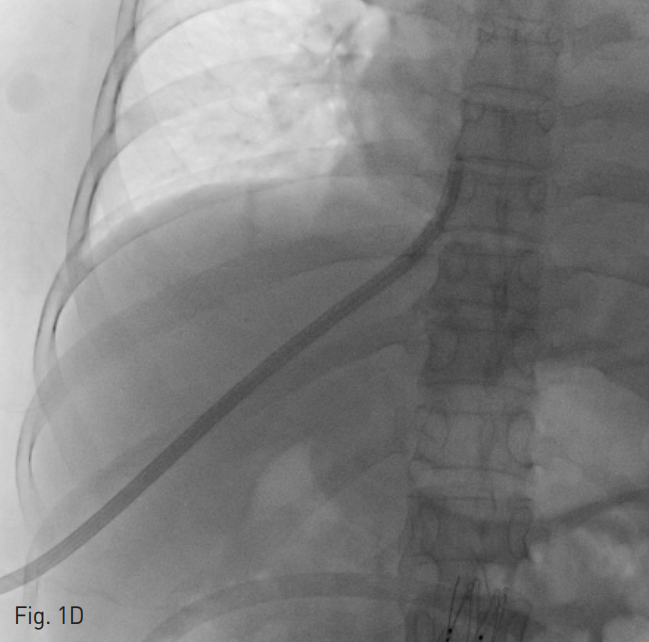

양측 내경정맥을 통한 정맥 조영술에서 상대정맥이 완전히 폐색되어 있으며 (Fig. 1A-B) 이를 대체하기 위해 우측 대퇴정맥에 투석용 카테터를 삽입하였지만 이 또한 10일 후 카테터 주변으로 혈전이 발생하였다(Fig 1C). 이어서 허리 경유 접근을 통해 투석용 카테터 삽입을 위해 하대정맥 천자를 시도하였으며 6 Fr sheath까지 들어간 후에 천자된 곳이 대동맥임을 알게 되어 대동맥에 stent-graft를 넣었다 (Fig. 2A). 투석이 급하여 일단 간정맥을 통하여 투석용 카테터를 삽입하였으나 (Fig. 1D) 이 역시 혈전으로 인한 기능 부전으로 수 차례 교환술을 시행하였다.

D. After failure of translumbar approach, the tunneled dialysis catheter was inserted through the right hepatic vein.